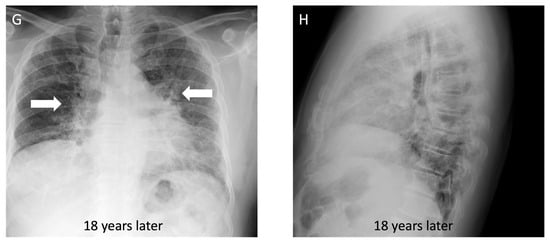

Figure 5.

A 43-year-old non-smoking male with 15-year history of tungsten carbide exposure as a metal grinding tool maker, diagnosed with hard metal lung disease, which was confirmed with surgical lung biopsy. (A,B) Axial computed tomography images demonstrate patchy ground glass opacities (arrows) and small centrilobular nodules (white circle) with minimal architectural distortion and traction bronchiectasis; (C,D) computed tomography images 18 years later demonstrate long-term evolution of fibrosis, with development of traction bronchiectasis (white circle) and mild honeycombing (black arrows) on the background of ground glass opacity and coarse reticulation; (E) posteroanterior view and (F) lateral view chest radiographs show a perihilar and lower lung zone predominant reticular abnormality (black arrows); (G) posteroanterior view and (H) lateral view chest radiographs 18 years later demonstrate a reduction in lung volumes, and the prior interstitial opacities appear coarser and more prominent, particularly in the perihilar lung (white arrows).